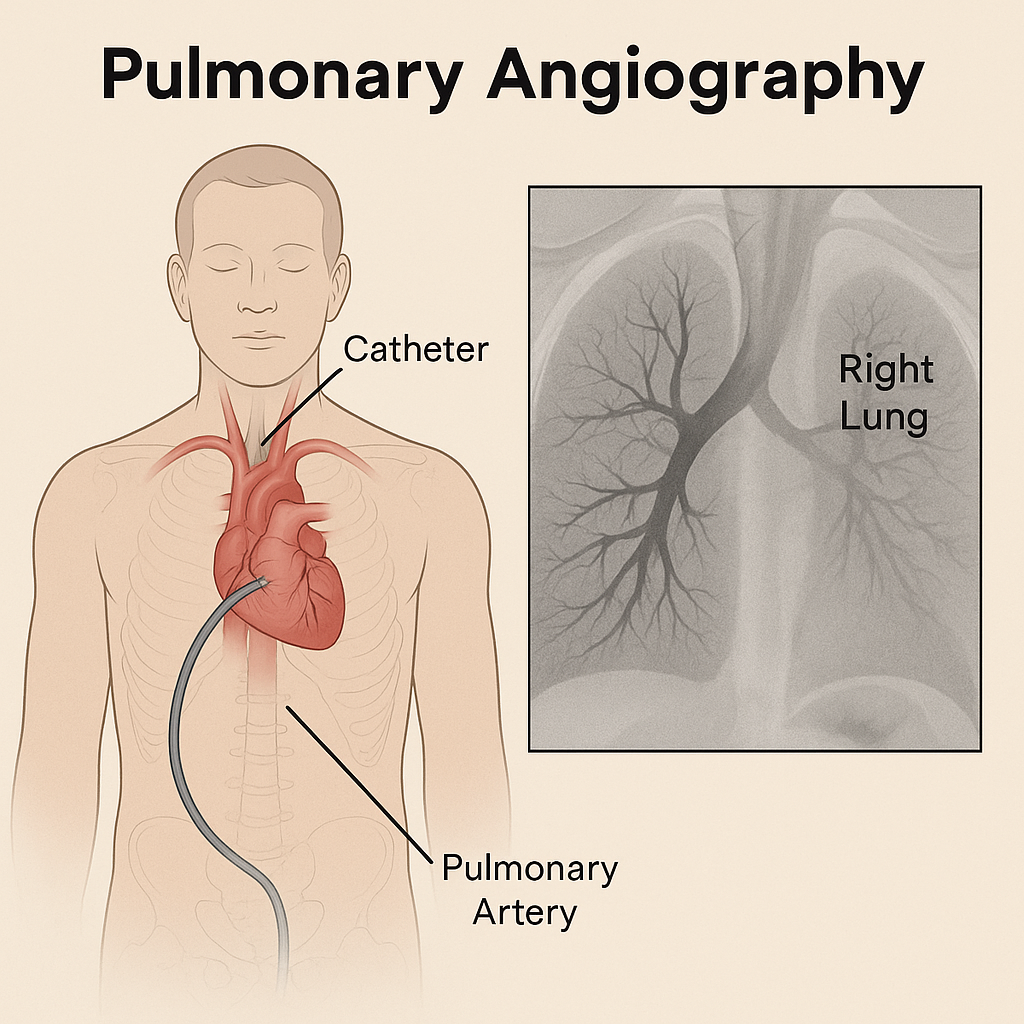

Pulmonary angiography (પલ્મોનરી એનજીઓગ્રાફી):

- આ એક ઇન્વેસીવ ફ્લુરોસ્કોપીક પ્રોસીઝર છે જેની મદદથી પલ્મોનરી વેઇન અને પલ્મોનરી આર્ટરીને વિઝયુલાઇઝ કરી શકાય છે.

- જેમાં ફિમોરલ આર્ટરી અથવા પલ્મોનરી આર્ટરીમાં કેથેટરની મદદથી કોન્ટ્રાસ્ટ ડાય ઇન્જેકટ કરવામાં આવે છે અને પલ્મોનરી વેસલ્સને વિસયુલાઈઝ કરવામાં આવે છે અને તેની સ્ટડી કરવામાં આવે છે.

- પલ્મોનરી એનજીઓગ્રાફીની મદદથી પલ્મોનરી એમ્બોલીઝમ, પલ્મોનરી વસ્કયુલર, પલ્મોનરી હાઇપરટેન્શન તેમજ પલ્મોનરી વસ્કયુલર ટ્રી ની એબનોર્મલીટી ડિટેકટ કરી શકાય છે તેમજ પલ્મોનરી બ્લડ ફલો, બ્લોકેજ, પ્રેશર અને એબનોર્મલીટીને ઇવાલ્યુટ કરવામાં આવે છે.